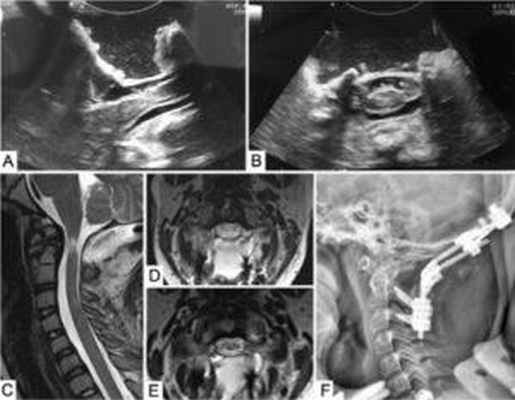

МРТ пациента с аномалией Киари и базиллярной импрессией. Красной стрелкой отмечено смещение зуба С2 позвонка, синей – смещение миндалин мозжечка ниже линии Чемберлена

КТ этого же пациента, на которой заштрихована зона предполагаемой трансназальной эндоскопической резекции.

КТ после операции – эндоскопически и через нос резецирован зуб С2 позвонка, выполнена передняя декомпрессия ствола головного мозга

Пример задней декомпрессии с последующей дистракцийе (вправлением) С2 позвонка и стабилизацией винтовой системой (интраоперационные УЗИ, МРТ и рентген после операции).

Материалы и методы. С 2014 по 2019 г. в Национальном медико-хирургическом центре им. Н. И. Пирогова было проведено хирургическое лечение 3 пациентов с сочетанием базилярной инвагинации и аномалии Киари I типа. Показаниями к операции были длительно прогрессирующие неврологические нарушения и неэффективность консервативной терапии. Выполнена передняя эндоскопическая трансназальная и задняя декомпрессия нервных структур с последующей стабилизацией.

Результаты. Состояние всех пациентов оценено через 12 мес после операции. У всех пациентов наблюдалась положительная динамика неврологического статуса. По данным магнитно-резонансной томографии краниовертебрального сочленения у 2 пациентов констатирована положительная динамика: регресс очага миелопатии, уменьшение диаметра сирингомиелической кисты.

Заключение. Передняя эндоскопическая трансназальная декомпрессия нервных структур показана при преобладании в клинической картине бульбарных нарушений и / или парезов конечностей, задняя декомпрессия – при наличии специфических симптомов аномалии Киари I типа и / или сирингомиелии. Принимая во внимание результаты последних исследований, можно предположить, что стабилизация является необходимой составляющей лечения пациентов с данными патологиями.